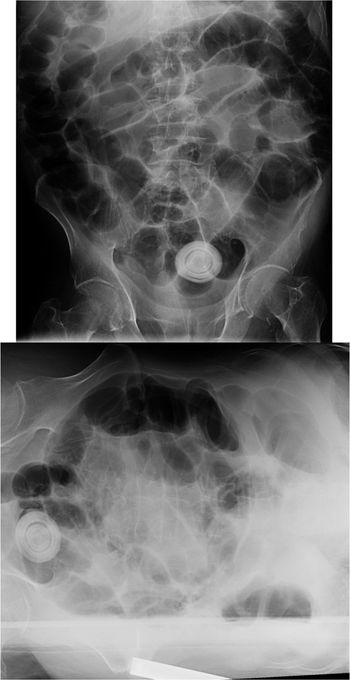

Three cases: A 98-year-old male with multiple co-morbidities presented with abdominal pain, fever and distension; Elderly female patient with right upper quadrant pain; A 50-year-old female with acute abdominal pain, r/o obstruction.